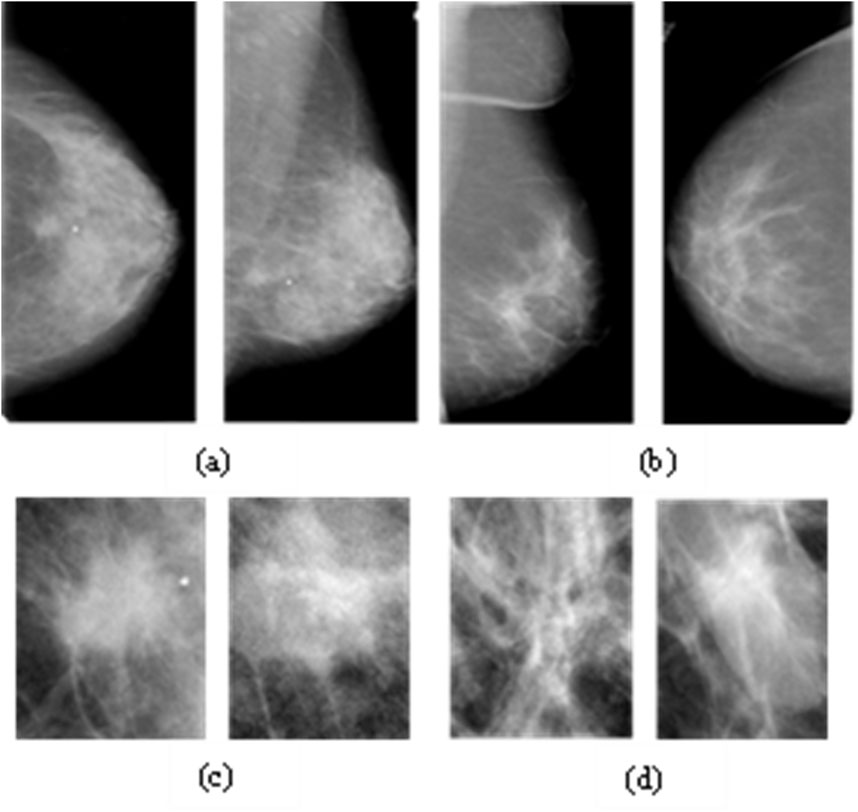

The CBIS-DDSM is a standardised and enhanced version of the original DDSM, designed to improve accessibility and utility for computer-aided diagnosis (CAD) research. It offers decompressed, full-field mammograms in DICOM format, accompanied by lesion masks and pathology-confirmed annotations reviewed by expert radiologists (Heath et al., 1998; Lee et al., 2017). CBIS-DDSM includes 1,644 cases divided into four categories: benign/malignant masses and benign/malignant calcifications. For this study, we focus exclusively on mass lesions to reduce heterogeneity. The training subset comprises 355 benign and 336 malignant mass cases, while the testing subset includes 117 benign and 83 malignant cases. The dataset’s high-resolution images, expert-reviewed segmentation masks, and structured diagnostic labels make it a valuable benchmark for deep learning-based breast cancer detection. Figure 7 shows representative samples from the CBIS-DDSM dataset.

Figure 7

Two rows of mammograms are displayed. The top row labeled (a) and (b) shows four images of breast tissue in profile view. The bottom row labeled (c) and (d) presents four more images focusing on specific areas, displaying varying tissue densities.

Figure 7. Examples from the CBIS-DDSM Dataset: Full and Cropped Mammograms for Malignant (a,c) and Benign Masses (b,d).